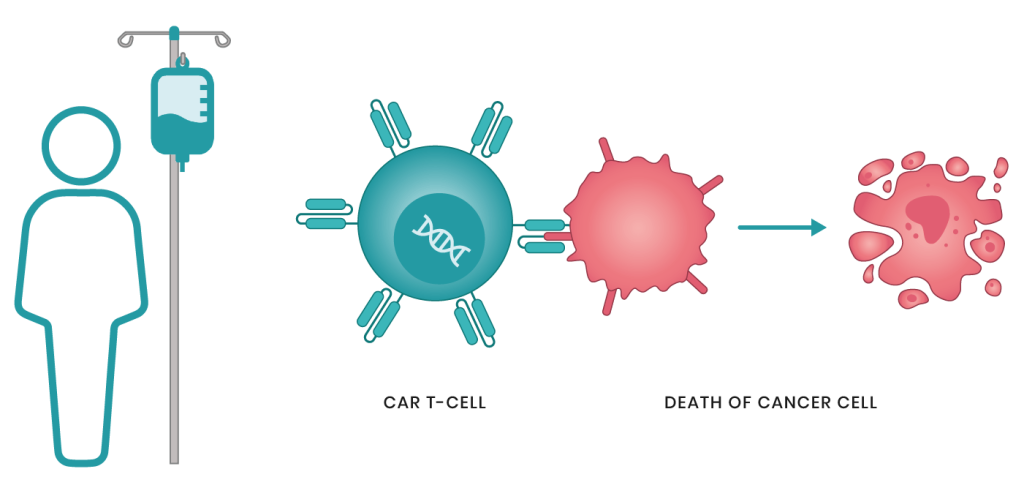

العلاج الخلوي التكيفي تم في عام 2017 الانتهاء من عدد من التجارب السريرية الكبيرة لتقنية علاج السرطان الجديدة، وهي العلاج بـ CAR T-Cell. وفقاً لنتائجهم، تمت الموافقة على اثنين من الأدوية: Kymriah و Yescarta. في الواقع يعد العلاج CAR T-Cell هو في وقت واحد علاجاً جينياً، ومناعياً، وخلوياً. تغير هذه التقنية خلايا الدم البيضاء للمريض بطريقة تمكنها من التعرف على الخلايا السرطانية وتدميرها. على الرغم من عدد من الآثار الجانبية، سيكون العلاج CAR T-Cell فعالاً بالنسبة لمعظم المرضى الذين لا يتقبلون أي علاج آخر أو في حالات الانتكاس.

يستخدم العلاج الخلوي CAR-T الكريات البيض الخاصة بالمريض لمكافحة الخلايا السرطانية. وفقاً لذلك، فإن المرحلة الأولى من العلاج تتمثل في الحصول على الكريات البيض للمريض – وهذا يحدث أثناء أخذ عينات الدم خارج الجسم وفصادة الكريات البيض (الحصول المباشر على الكريات البيض من الدم). بالإضافة إلى جمع الكريات البيض، فإن تكوينها النوعي مهم. وعلى وجه الخصوص، تتم إزالة الوحيدات من العدد الكلي للكريات البيض، والتي تعوق في البيئة الطبيعية تنشيط وتكاثر الخلايا التائية اللازمة للعلاج العلاج الخلوي CAR-T.

بعد تلقي كريات البيض المحدثة التي تحتوي على CAR، يتم تكاثر الخلايا في المختبر. يعد إدخال عدد كاف من الكريات البيض النشطة مع CAR شرطاً أساسياً للعلاج الفعال. هذه المرحلة المختبرية هي الأكثر استهلاكاً للوقت ويمكن أن تستغرق ما يصل إلى 22 يوماً.

قبل إعادة إدخال الكريات البيض المحتوية على CAR يتم إعطاء المريض دورة من العلاج الكيميائي تهدف إلى تقليل عدد الكريات البيض الخاصة بهم. تسمح هذه الظروف بتضاعف الكريات البيض “الخاصة” التي يتم إدخالها بشكل مكثف أكثر. عند تنفيذ العلاج الخلوي CAR-T، فإن دورة واحدة فقط من معالجة جينوم الكريات البيض تكون كافية. في المستقبل تتكاثر خلايا الدم البيضاء بنفسها في دم المريض، مما يوفر مناعة دائمة ضد الانتكاس.